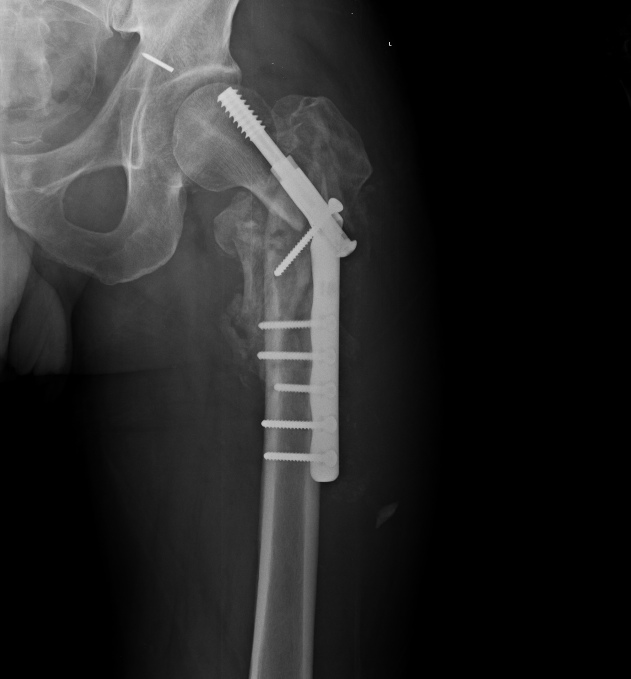

Спасибо за интересное обсуждение. Действительно, головка сохраняет сферичность, кровоснабжение ее должно быть сохранено, так что есть смысл сделать реконструкцию.

Удалили DHS, пришлось вытащить единым блоком, винт прокручивался. . Опознавательных знаков на имплантате не обнаружили. Дополнительный винт был введен во фрагмент, который оказался не связан ни с чем, так что удалили и его После удаления была хорошая подвижность. Сделали остеосинтез вот так. Комментарии и критика приветствуются.